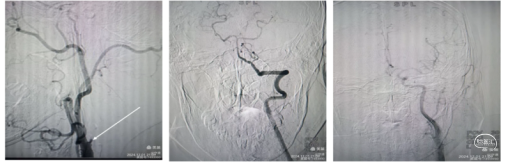

手术过程:经股动脉穿刺,置入8F动脉鞘术中造影左侧颈内动脉重度狭窄,颈内血流迟缓。

微导丝携带微导管尝试通过狭窄到达M1段微造影远端血管通畅。通过6F长鞘颈总动脉造影颈内动脉全程通畅,仅仅为颈内起始部重度狭窄。考虑颈内动脉ICAS病变,静脉溶栓再通但不畅。微导丝携带微导管通过狭窄部位改善了血流。

球囊扩张血管成形 3mmx15、4.5mmx15球囊扩张颈内动脉狭窄部位,造影显示狭窄改善,全程血流通畅且快速,Ⅰ未植入支架,推注替罗非班10mL,造影未见远端血管血栓逸逃征象,结束手术。药物治疗观察必要时Ⅱ期支架植入血管成形。

回撤5F中间导管于颈总动脉造影显示颈内动脉起始段重度狭窄。(下图1)

在C1段置入5mm保护伞,用3mm和4mm球囊扩张狭窄部位,但撤出球囊后狭窄略有改善。(下图2)

置入6~8~40mm自膨支架,支架位置良好,残余狭窄约30%。(下图3)

回撤导管与颈总动脉造影支架位置良好,远端大脑中动脉显影良好,分叉部无明确血栓征象。可能经替罗非班推注和血管通畅后逃逸的小血栓溶解了。再通后流动的血液就是最好的溶栓剂。